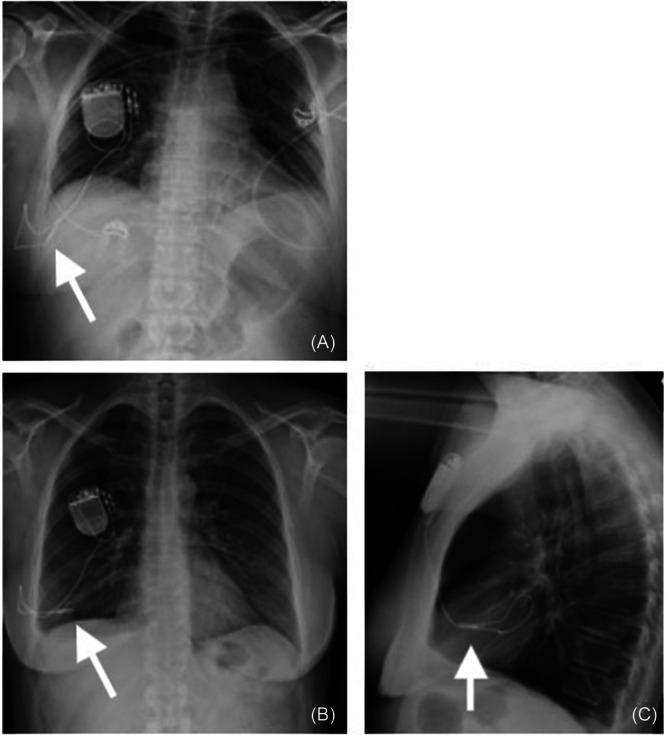

Results: In total, 151 out of 765 HGNS adverse events were related to the respiratory sensing lead, and of those, 75 were related to lead migration. There were seven events related to migration of the sensing lead into the pleural space, of which six cases underwent revision surgery (<1% of adverse events reported related to HGNS). Two cases noted pneumothorax due to sensing lead migration. We report two cases of sensing lead migration at our institution. Migration was demonstrated with serial imaging. These cases highlight the potential need for preoperative or intraoperative chest tube placement, based on the extent of migration, complications, and complexity.